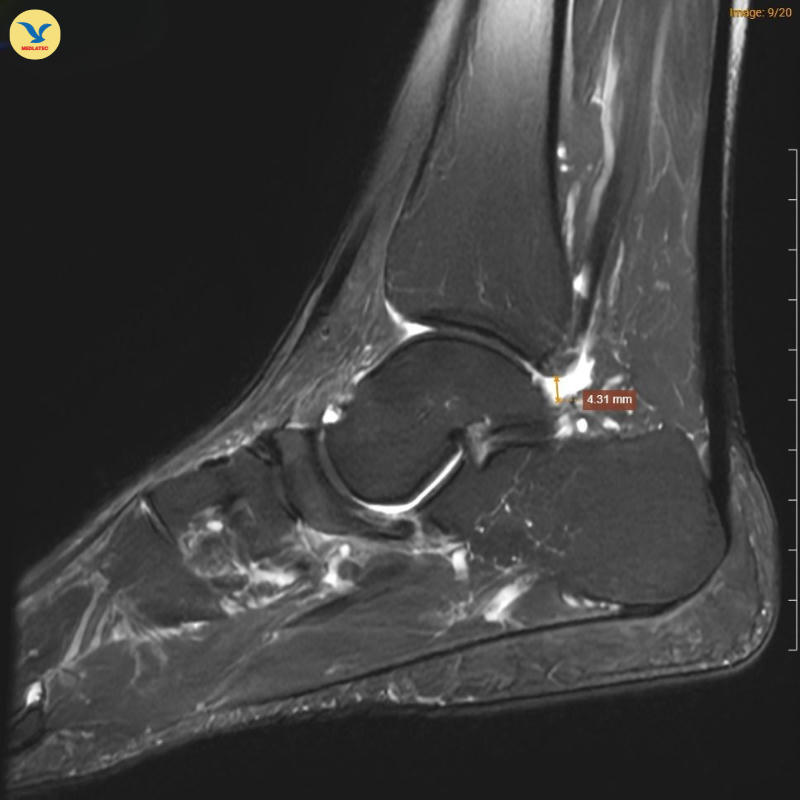

Tại MEDLATEC, bác sĩ đã chỉ định chụp Cộng hưởng từ (MRI) để tìm kiếm những tổn thương sâu trong cấu trúc xương. Trên lát cắt Sagittal T1W, hình ảnh cho thấy xương ghe bị xẹp và biến dạng điển hình hình dấu phẩy, kèm theo tình trạng đặc xương dưới sụn. Trên chuỗi xung T2W FS, ghi nhận tình trạng phù tủy xương ghe rõ rệt.

Đồng thời ghi nhận hình ảnh tổn thương gai xương thoái hóa khớp cổ chân trái, ổ phù tủy xương vị trí xương sên, phù nề dây chằng chày mác sau, dây chằng sên mác sau, dây chằng gót chày và dây chằng tam giác cổ chân, dịch khớp cổ chân, phù nề phần mềm quanh khớp cổ chân.